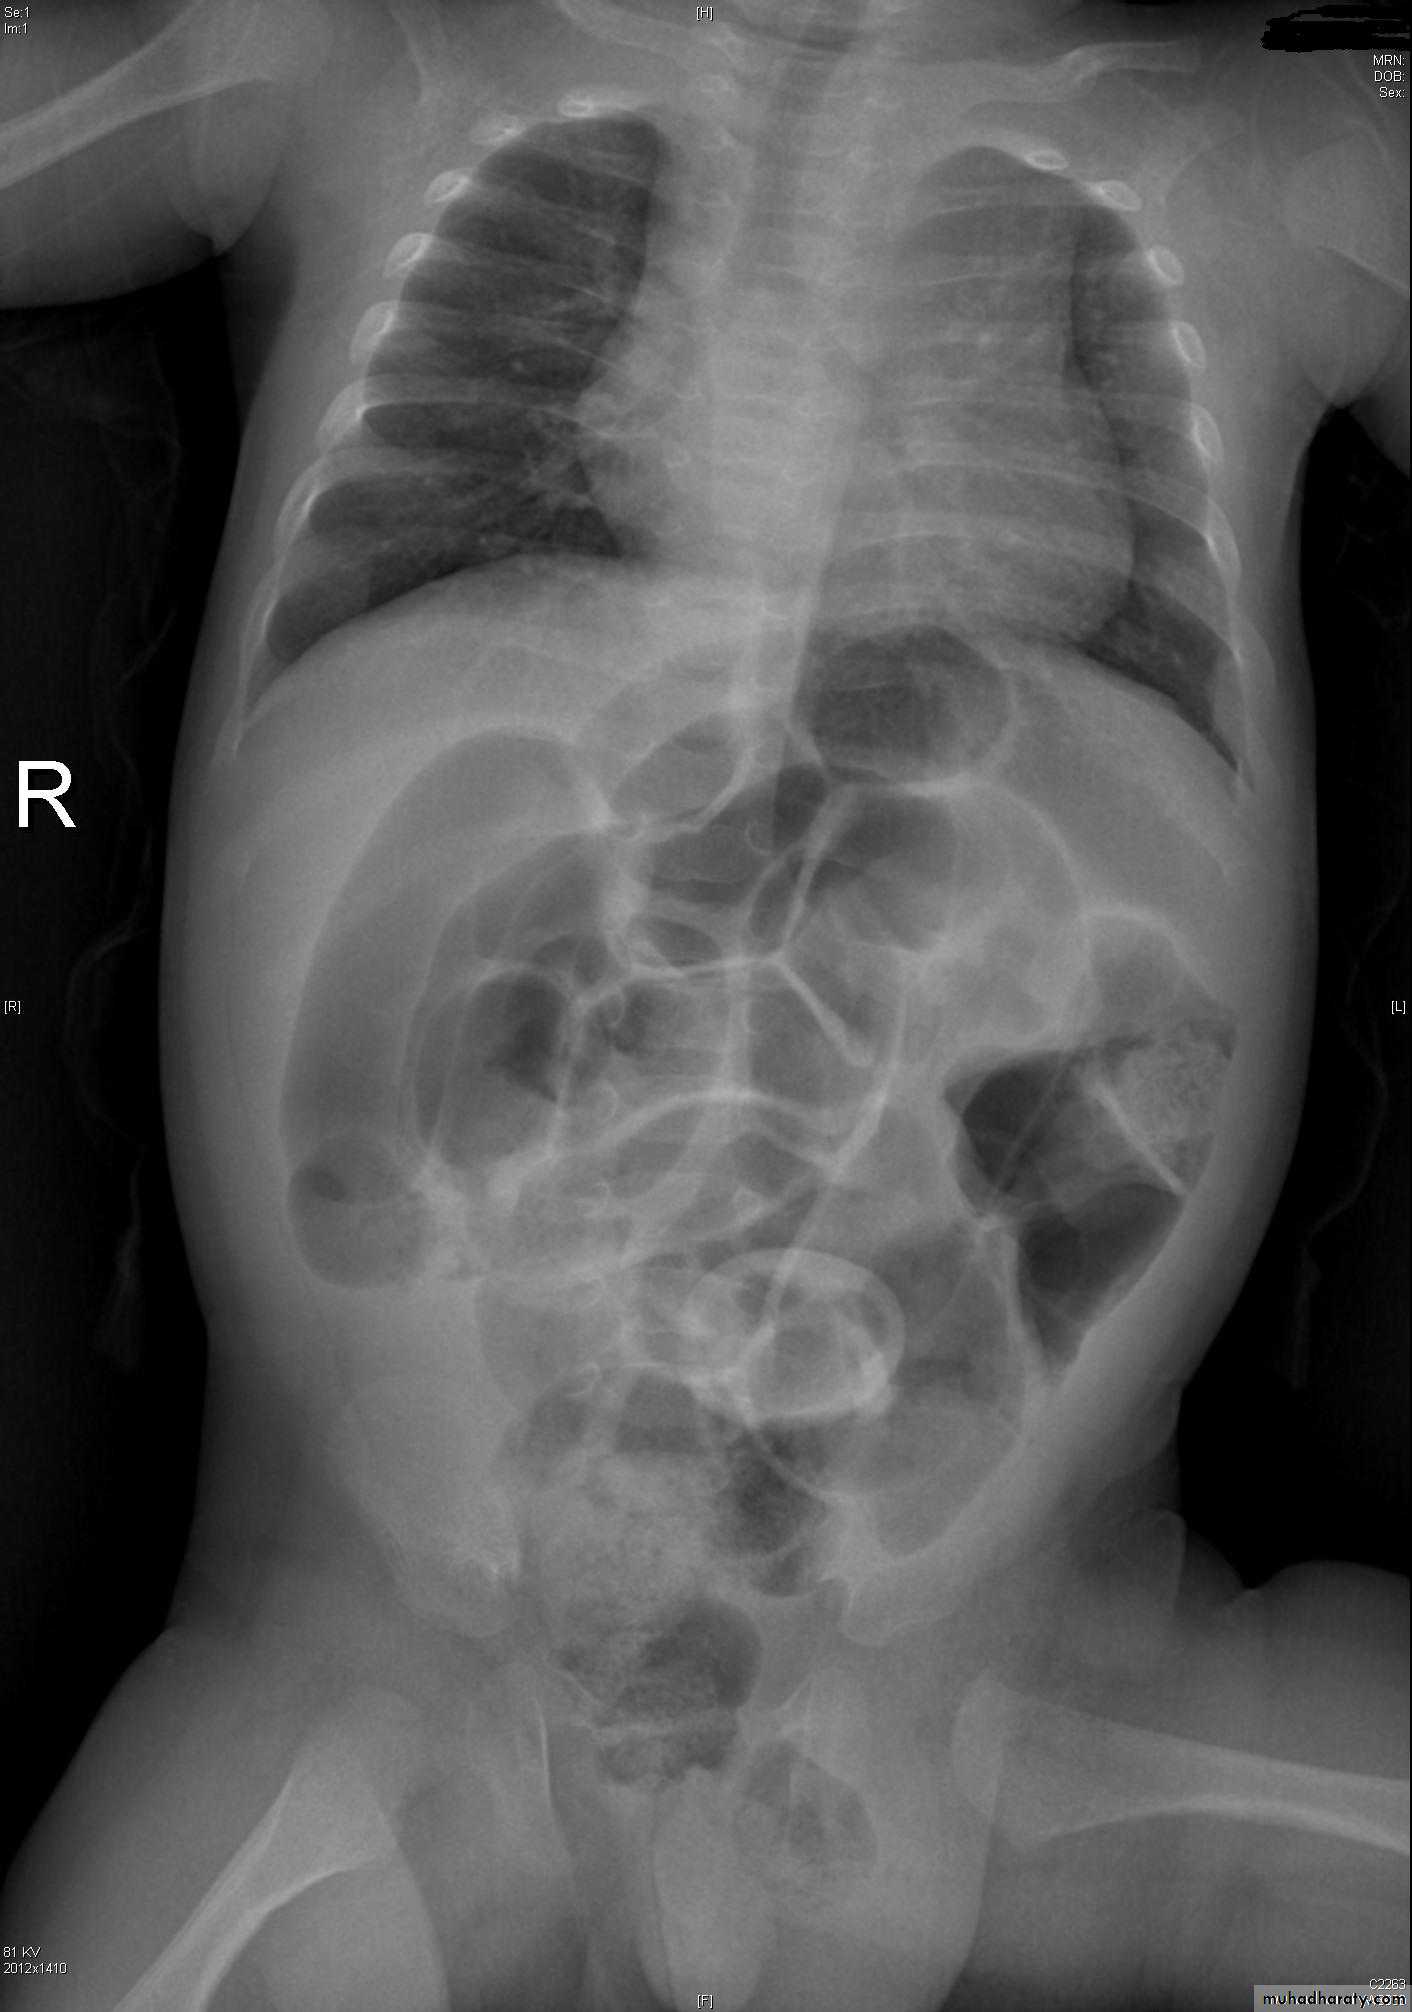

Paralytic ileus

• Differential diagnosis of dilated small bowel loops on AXR is paralytic ileus.

Paralytic ileus may be generalized or localized.

• Localized ileus refers to dilated loops of bowel (‘sentinel loops’), usually small bowel, overlying a local inflammation:

• Right upper quadrant: acute cholecystitis

• Left upper quadrant: acute pancreatitis

• Lower right abdomen: acute appendicitis.

• Generalized ileus refers to non-specific dilatation of small and large bowel, which may occur postoperatively or with peritonitis.

• Scattered irregular fluid levels are seen on the erect X-ray.